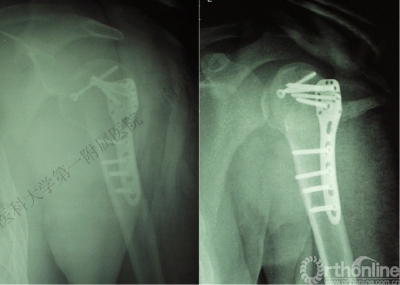

病例3

男性,27岁,车祸致右肩部肿痛、活动受限6小时。

术后肩关节X线片

病例2

VS

四、分型

肩关节后脱位:

Ⅰ型: +肱骨颈骨折。

Ⅱ型: +肱骨颈骨折+小结节骨折(病例3)。

Ⅲ型: +肱骨颈骨折+小结节骨折+大结节骨折(病例2),以骨折线向肱骨近端外侧壁延伸为另一特征。

五、反Hill-Sachs 损伤对肩关节稳定性的影响